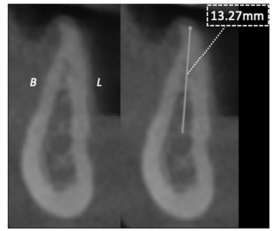

A imagem a seguir corresponde a uma tomografia computadorizada de feixe cônico com a finalidade de planejar uma reabilitação dentária implantosuportada na região edêntula do primeiro molar inferior direito. A linha vertical demonstra a medida da altura óssea disponível para a colocação do implante, que vai do topo da crista óssea até o osso cortical superior da mandíbula.

A imagem apresentada permite a seleção do implante dentário e, em especial, sua extensão, considerando-se a proximidade com áreas anatômicas de risco e o baixo perfil de distorção dimensional existente nas tomografias de feixe cônico em torno de 10% da imagem real.